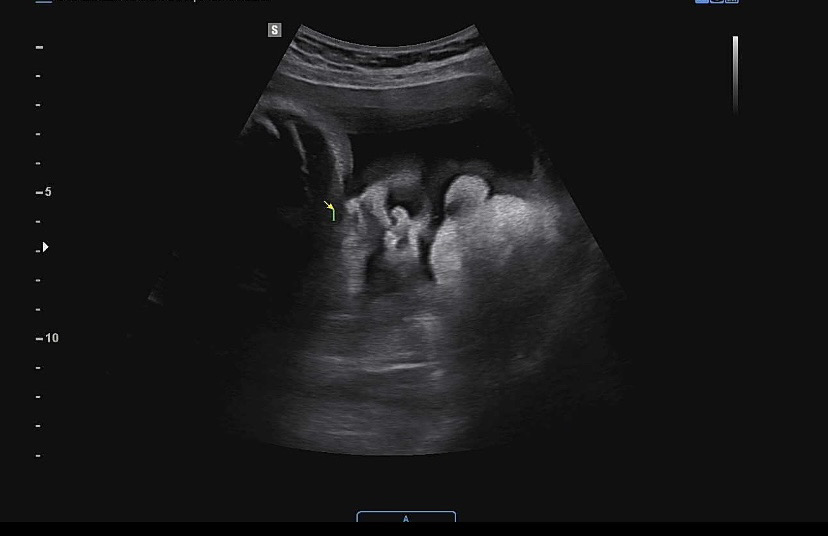

34주이고 촘파보고 왔는데 원장님이 눈이랑 코랑 보인다고 하시는데 입은 손으로 가려져 있고 근데 전 아무리 봐도 눈 코가 안보여요 ㅠㅠ 보이시는 분 계신가요? 저도 애기 얼굴보고 싶은데 모르겠네효…ㅋㅋ

흐규 😭 뽕뽕 뚫린 두 개의 커다란 검정 구멍이 아기 안구 (눈)라고 생각하시면 되세요. 무튼 날씨가 더운데 건강 관리 조심하시구 순산하시길~ ❤️ 🤍

보통 오른쪽 방향으로 애기 얼굴이 🤔 보이는데 아무리 봐도 모르겠어서 , 왼쪽으로 보면 애기 얼굴 같네요~ ㅎㅎ 설명하려고 그림판으로 그렸는데 대충 그려 가지구 ㅜㅜ 이해 되셨길 바라용